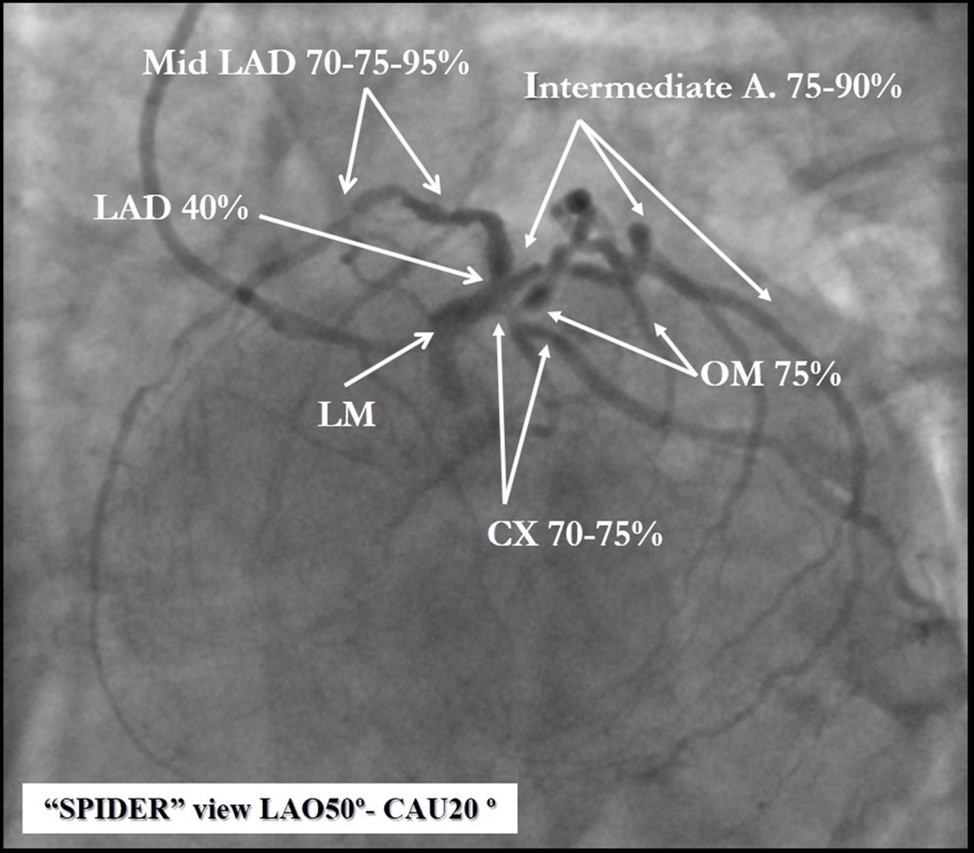

Angiography revealed rare anatomical variation LMCA quadrifurcation (Figure 1, Figure 2), 50% stenosis of the distal part of the LMCA, 40% stenosis of the ostial segment of left anterior descending (LAD) artery and diffuse prolonged 70-75-95% stenosis in mid-segment (Figure 3), 75% stenosis of the ostial segment of the circumflex (CX) artery, 75% stenosis of the ostial segment of the first marginal branch (OM1), 75-90% stenosis of the proximal segment of the intermediate artery (IMA), prolonged diffuse severe 90-95% stenosis of mid-segment of the right coronary artery (RCA) (Figure 4).

Due to financial problems the second stage was performed after 3 months (during this time the patient solved his financial problems). CAG revealed patent stents in LAD (Figure 7), and 60-70% restenosis by BMS in RCA (Figure 8). In-stent restenosis was treated by plain old balloon angioplasty (POBA), the optimal result was obtained (Figure 9). After LMCA quadrifurcation balloon predilation, 2.5×26 mm DES (Resolute Integrity, Medtronic) was implanted in the IMA, using a modified balloon mini-crush technique. The stent was minimally protruded in the LMCA and its edge was crushed by preloaded MB balloon. Next 2.5×30 mm DES (Resolute Integrity, Medtronic) was implanted in OM1 through the CX (first marginal and circumflex arteries in this particular case have the same ostium). The stent was protruded in the LMCA as in conventional modified balloon crush stenting technique, after stent deployment, its balloon was pulled back and overinflated, then protruded stent was crushed by preloaded MB balloon (Figure 10). 3.5×15 mm DES was implanted in the LMCA so that distal part of the stent covered ostial and proximal segments of the LAD. Sequential post-dilatations were performed using a kissing balloon technique (1. LMCA-LAD-IMA,2. LMCA-LAD-CX-1OM). After post-dilatations, through the stent implanted in CX-OM1, coronary wire and smaller diameter balloon (2.0 mm) were advanced in direction of the CX mid-segment and by balloon dilatation stent’s strut was opened (provisional stenting technique for CX). Finally, the proximal optimization technique was performed in the LMCA using a 3.5 mm diameter non-compliant balloon (Figure 11). The final angiographic image was good, the intervention ended without complications (Figure 11, Figure 12). We could not confirm the result with IVUS or OCT due to several technical and financial problems (not covered by insurance). 1 month after PCI, at regular checkout, the ejection fraction was 48%, the functional class of the Congestive Heart Failure decreased from class II-III to class I and the patient complaints have been disappeared.